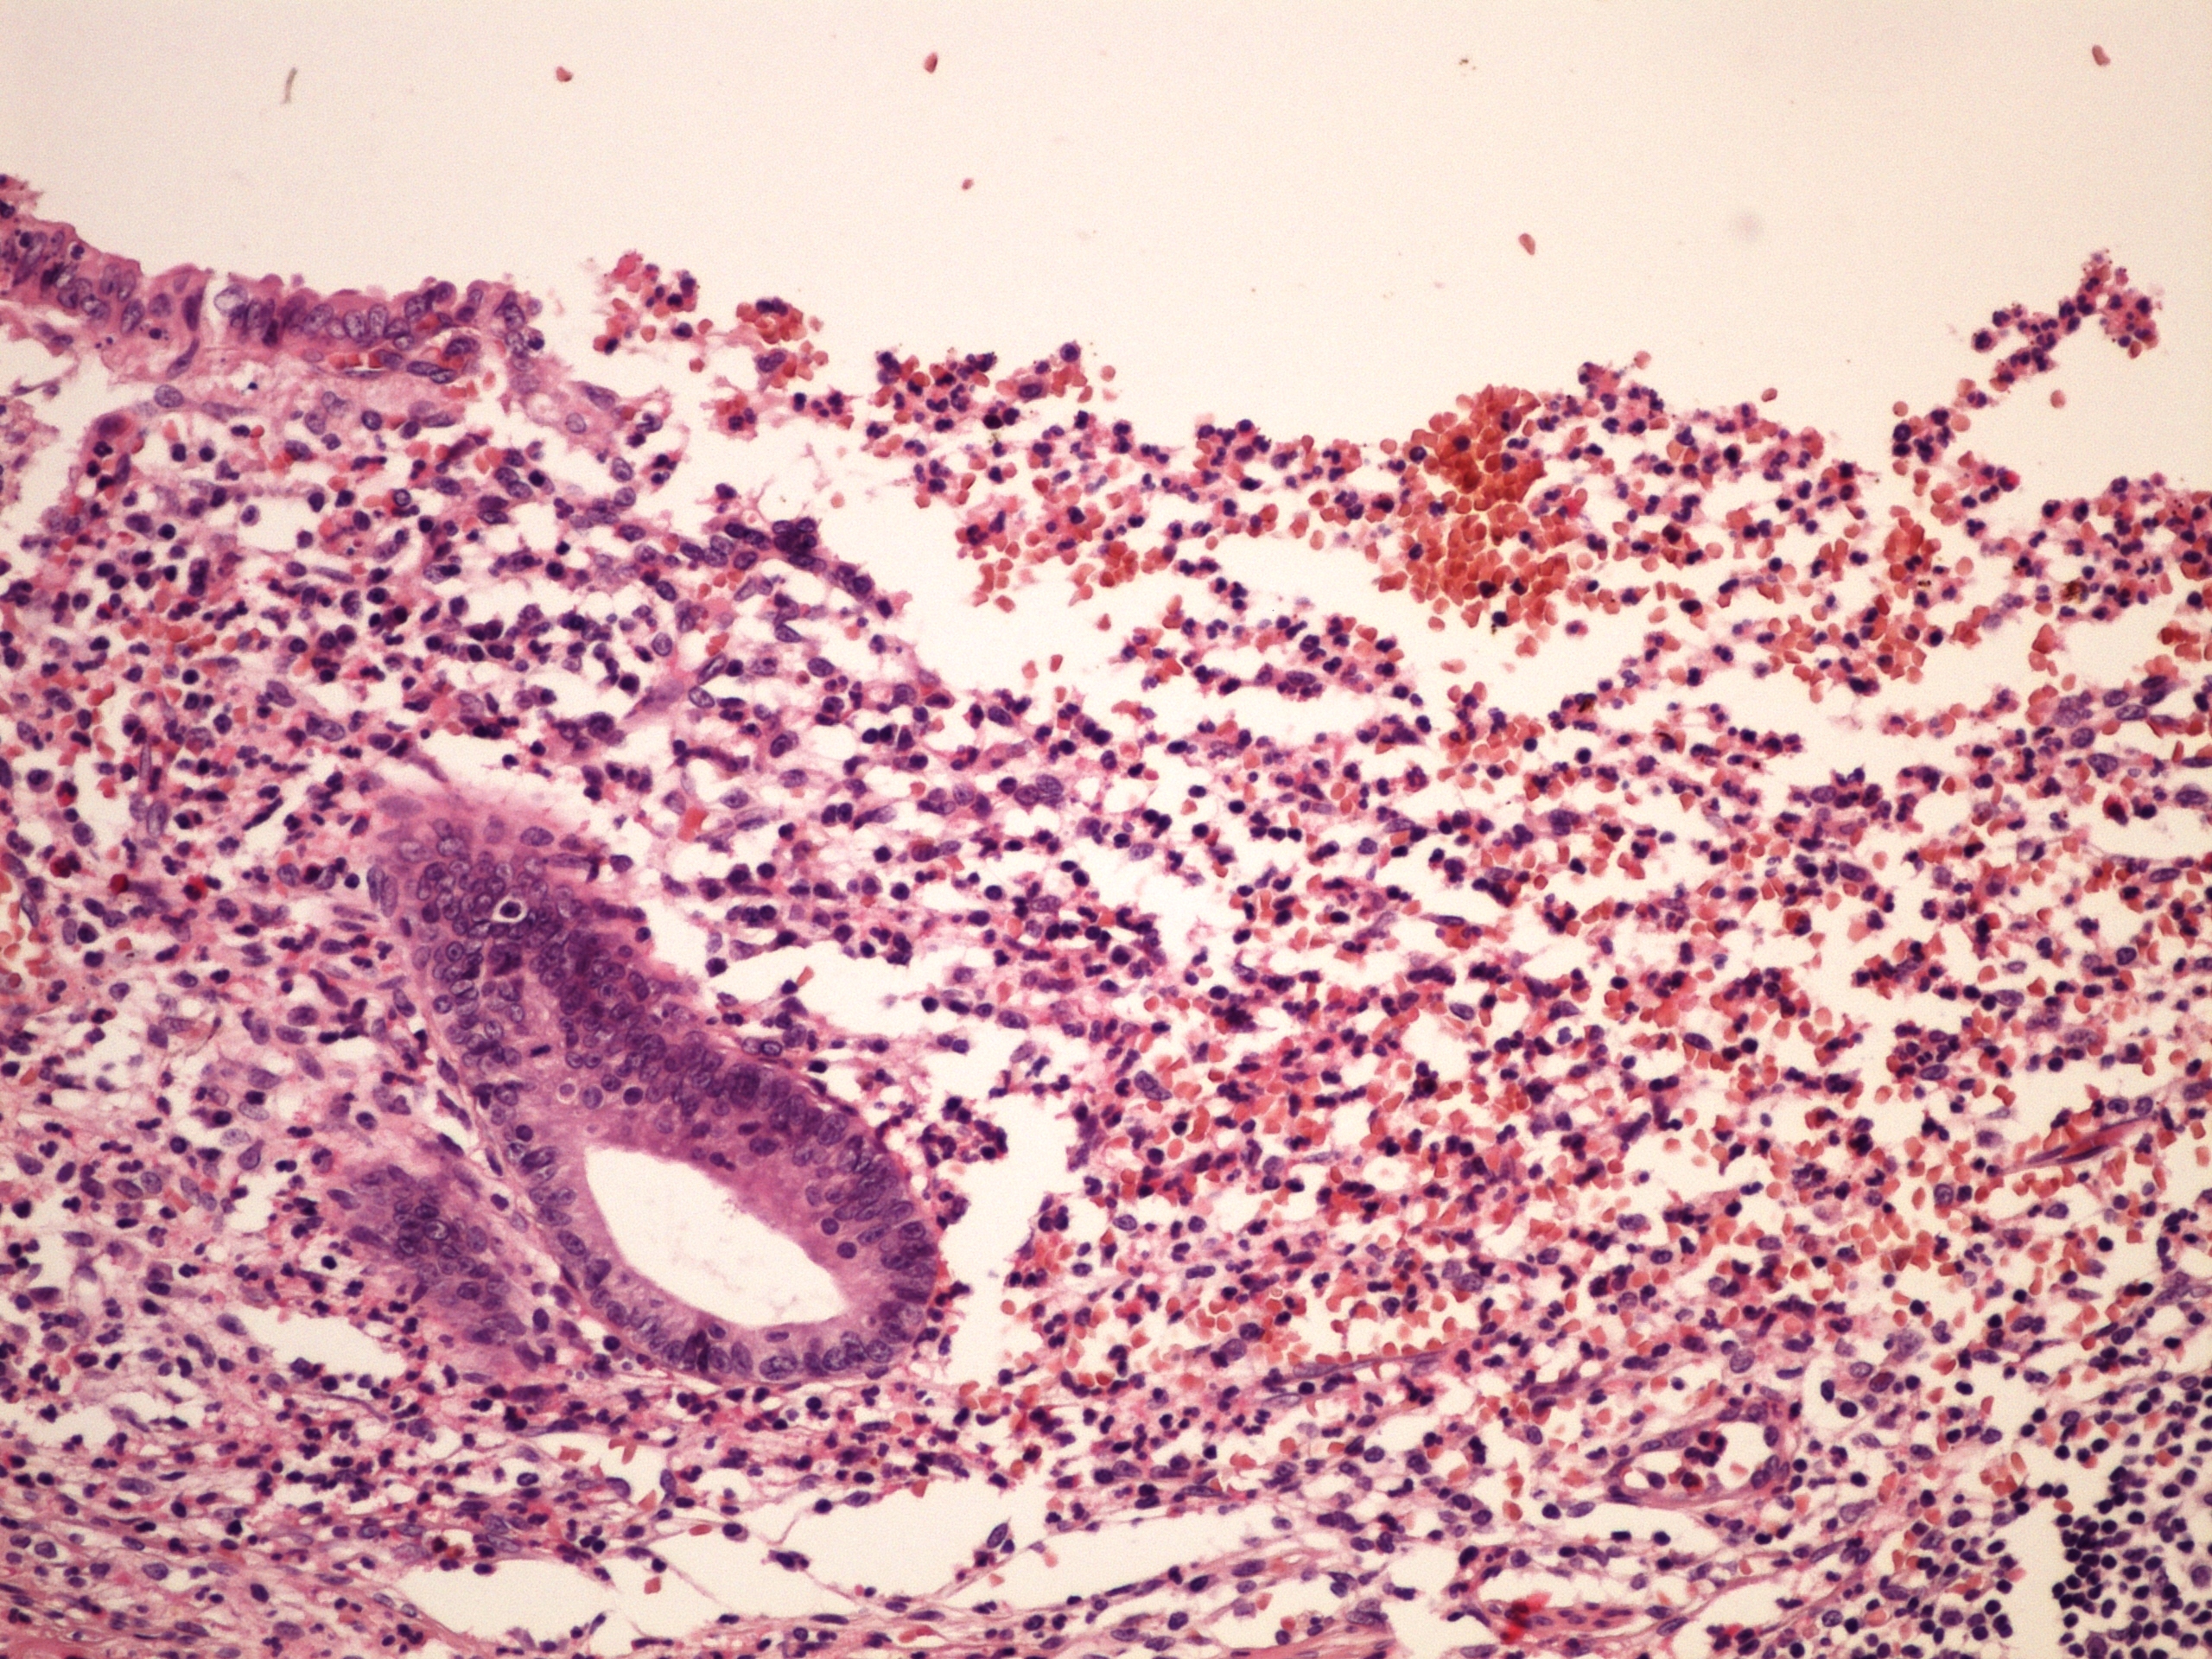

Preparát č.11 a č.12 - ulceroflegmonósní appendicitis

Struktury

- exsudát v lumen appendix vermiformis

- ulcerace

- flegmonózní infiltrace